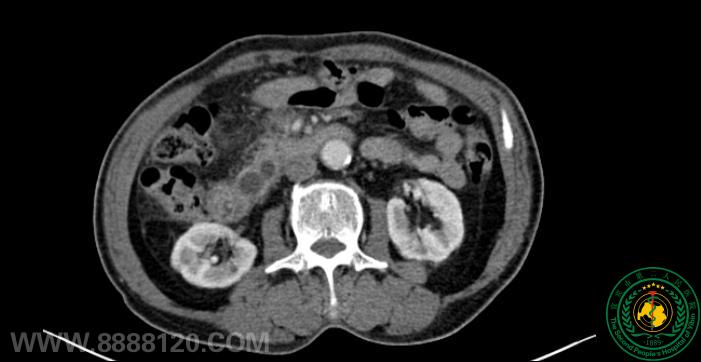

案例一:患者68岁男性,因“持续性上腹疼痛16天”入院。入院后查胰腺炎及肿瘤标志物均正常,磁共振CT均提肝内外胆管及主胰管扩张,没有发现明确占位病变超声内镜检查发现了一个大小约1.9×1.2cm的胰腺微小肿瘤。

CT